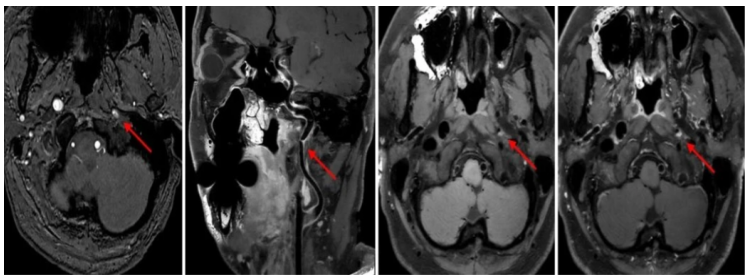

王大爷 10 天前突然感觉头晕,走路也变得不太稳,就像踩在棉花上一样,同时伴有恶心,双耳也像被塞住了一样闷闷的。

来我院就诊,经过磁共振的 MRA 及高分辨血管壁成像检查后发现,左侧颈内动脉 C1 段重度狭窄(动脉粥样硬化性)。

凭借 3.0T 磁共振的高场强优势,能提供亚毫米级的高分辨率,清晰显示血管壁的结构、厚度以及血管壁上的病变(如斑块);还能评估血管狭窄程度,更能深入分析动脉粥样硬化斑块的成分(如脂质核心、纤维帽、出血、钙化等)和稳定性(是否为易损斑块)。

最值得一提的是,这位「侦探」的本事可不小:假如有人突然头晕呕吐,常规检查说血管堵了,但它一上手有可能便能找到「罪魁祸首」——导致堵塞的是不稳定斑块还是其它,这可以为临床的进一步治疗提供关键依据;同时它还能鉴别血管炎、烟雾病、脑动脉夹层以及对动脉瘤风险的评估等有重要价值。